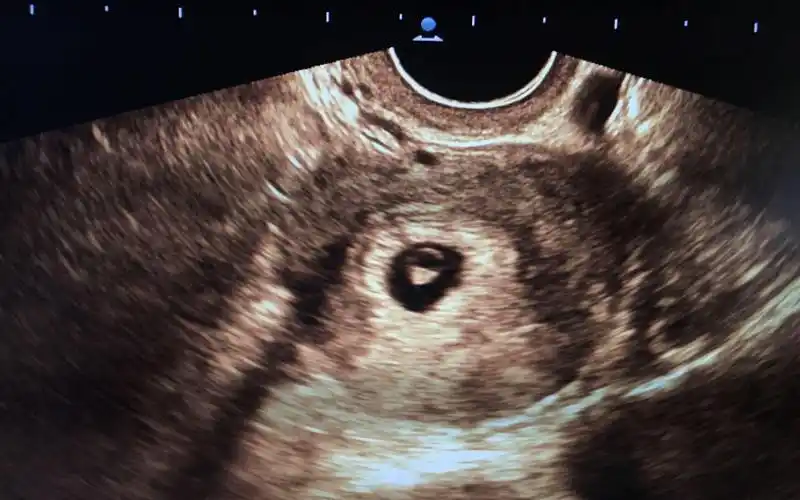

六周的孕囊能看出怀几个孩子吗孕早期通过孕囊形状看男女不靠谱

孕囊的形状一般是呈椭圆形或者是月亮型.